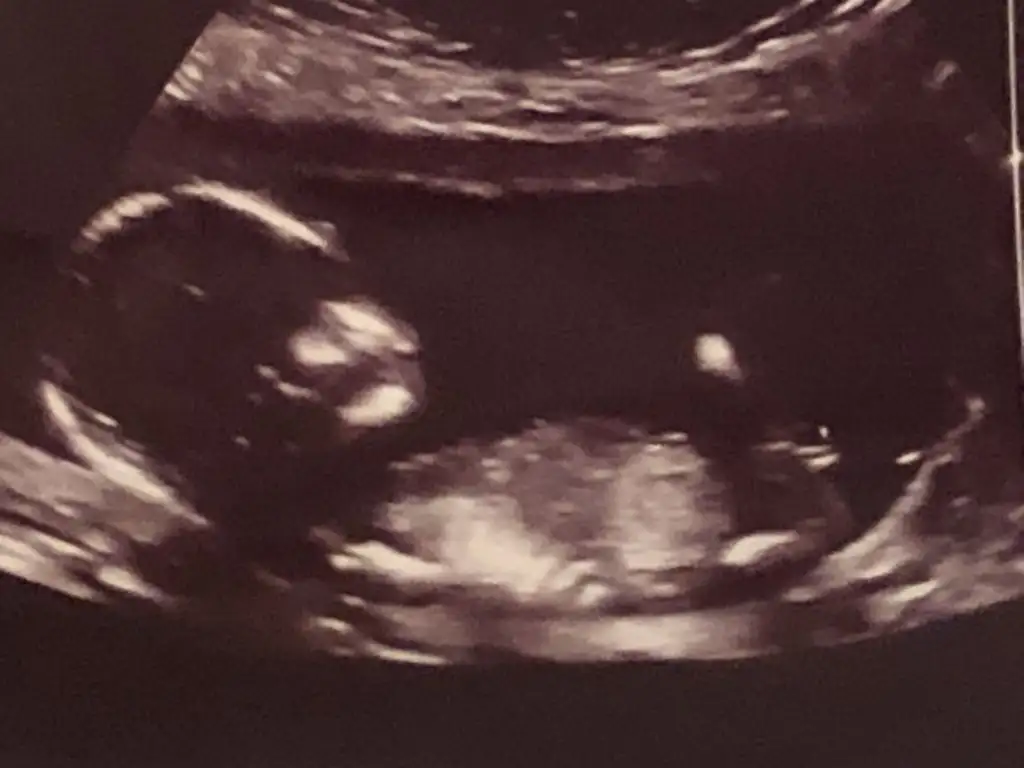

merhaba

9+5 karından usg cinsiyet tahmini yapabilir misiniz lütfen 🌸

image.webp